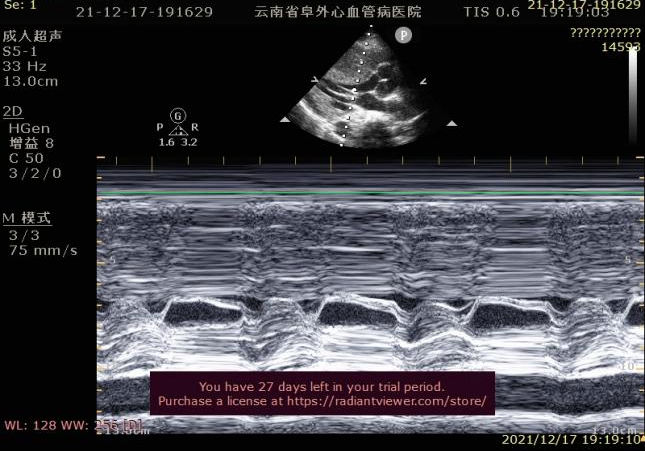

超声检查图像

心尖五腔心切面:连续多普勒测量左室流出道收缩期血流速度加快,频谱形态呈“倒匕首”样。

超声诊断:肥厚型梗阻性心肌病(室间隔基底部),二尖瓣少量反流。